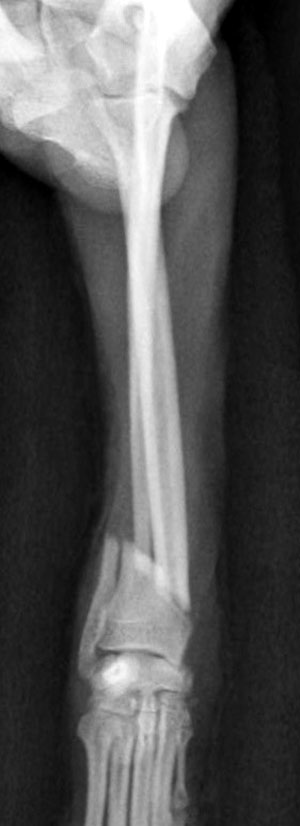

左前腕骨折のトイプードルちゃんの手術がありました。橈尺骨骨折は動物病院では一番よくある骨折です。ロッキングプレートであるTAITANコンディラー1.7mmで対応しました。治りも順調で元気に帰りました。よかったね。